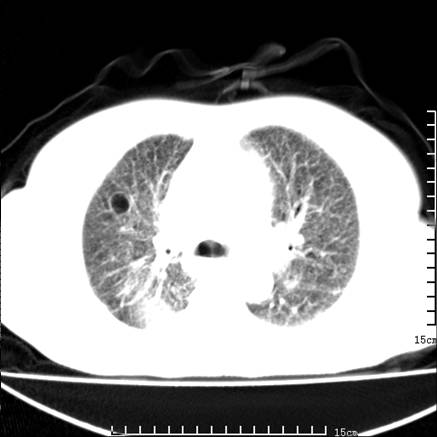

女,王某,58岁,咳嗽三个月余,基层医院二个月前诊为肺结核,用抗结核药二个月无明显疗效。

心包积液致肺瘀血.右侧周围型肺癌伴肺内转移,中间裂积液,叶间胸膜肥厚.右上肺大泡,右侧胸膜肥厚.

双肺继发型tb,心功能不全并肺淤血、心包、双侧叶间裂积液,肺大泡,右下胸膜肥厚钙化。

支持  双肺继发型tb,心功能不全并肺淤血、心包、双侧叶间裂积液,肺大泡,右下胸膜肥厚钙化。